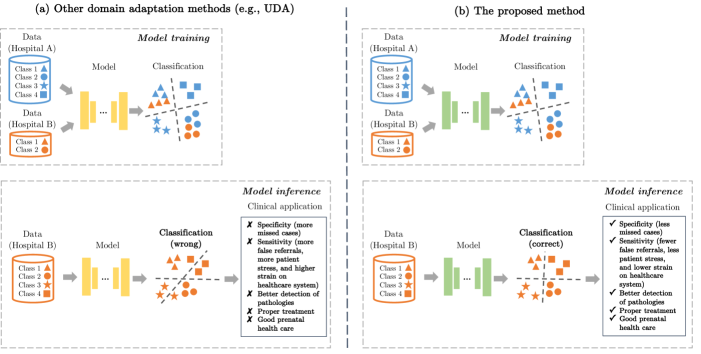

In contrast to the human visual system, DNNs exhibit weak generalizability when confronted with previously unseen entangled image features. This is the problem which we address in this paper. We postulate that DNNs should be able to learn generalizable features to transfer the knowledge from known entangled image features to new entangled image features. As outlined in Fig. 1, we want to improve the performance of DNNs on unseen categories in a target domain where all categories from a source domain and a subset of categories from a target domain are available for training. This task can greatly contribute to diagnostic classification in medical imaging. For example, detecting a certain pathology which rarely occurs in a particular geographic region but might be common in other places.

Therefore, we need domain adaptation methods to reliably transfer models from one clinical site to another and understand their error margins. Fig. 16 shows the utilization of deep learning models in clinical scenarios with and without domain adaptation.

Specifically in our work, the proposed method is applied to a real-world clinical application, the classification of standardized fetal ultrasound views during prenatal screening. Standardization of anatomical view planes is key to empower the front-line-of-care during screening, making measurements comparable across patients and to accurately predict outcomes. We focus on domain adaptation between fetal ultrasound datasets with different feature distributions, which are caused by imaging artifacts and different acquisition devices. Our study enables learning-based classifiers to be effectively utilized on a wider range of fetal ultrasound images. This helps early detection of pathological development independent from the used imaging setup. The detection of abnormalities can inform downstream treatment decisions and delivery options [25]. Fig. 17 illustrates and compares the potential impact of our method and other domain adaptation methods on machine learning for patient care in the context of fetal screening.